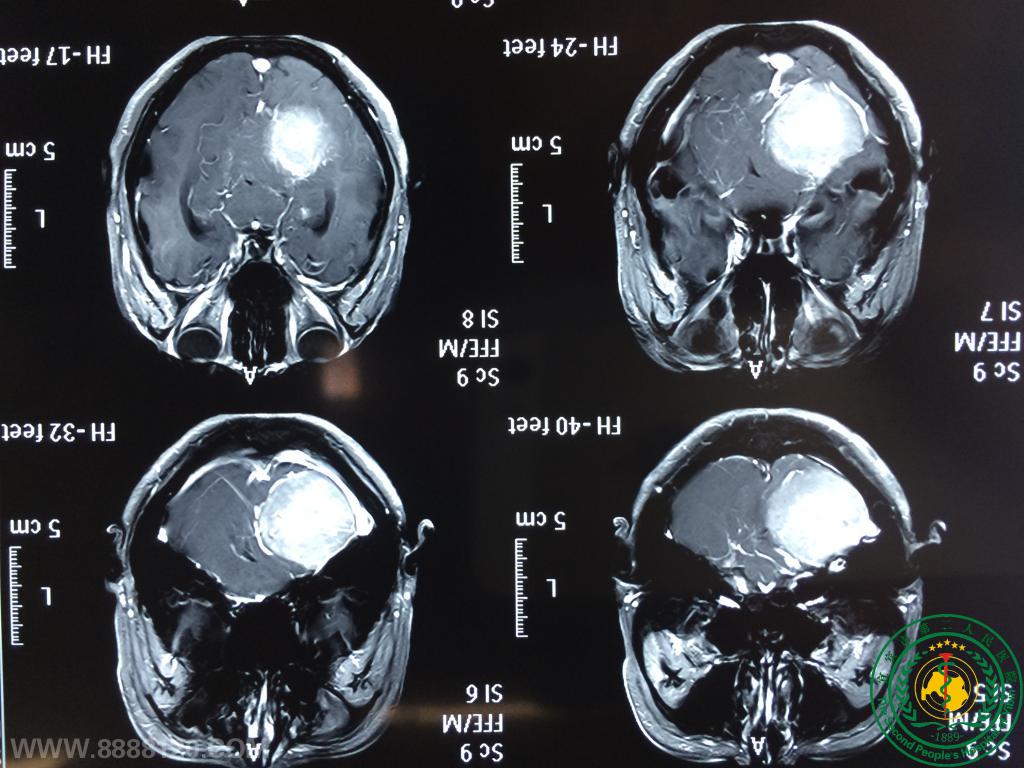

我科应用无水乙醇+美兰瘤内注射示踪止血技术完成1例CPA区巨大高血运脑膜瘤手术

我科应用无水乙醇+美兰瘤内注射示踪止血技术完成1例CPA区巨大高血运脑膜瘤手术9071